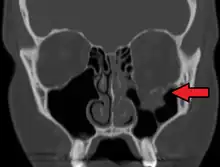

Le diagnostic est fait sur le scanner facial.

Fracture de type blow-out

L'ouverture du plancher de l'orbite est large et comminutive. En l'absence de fracture de la margelle infra-orbitaire, le blow-out est dit pur. Sinon, il s'agit d'un blow-out impur.